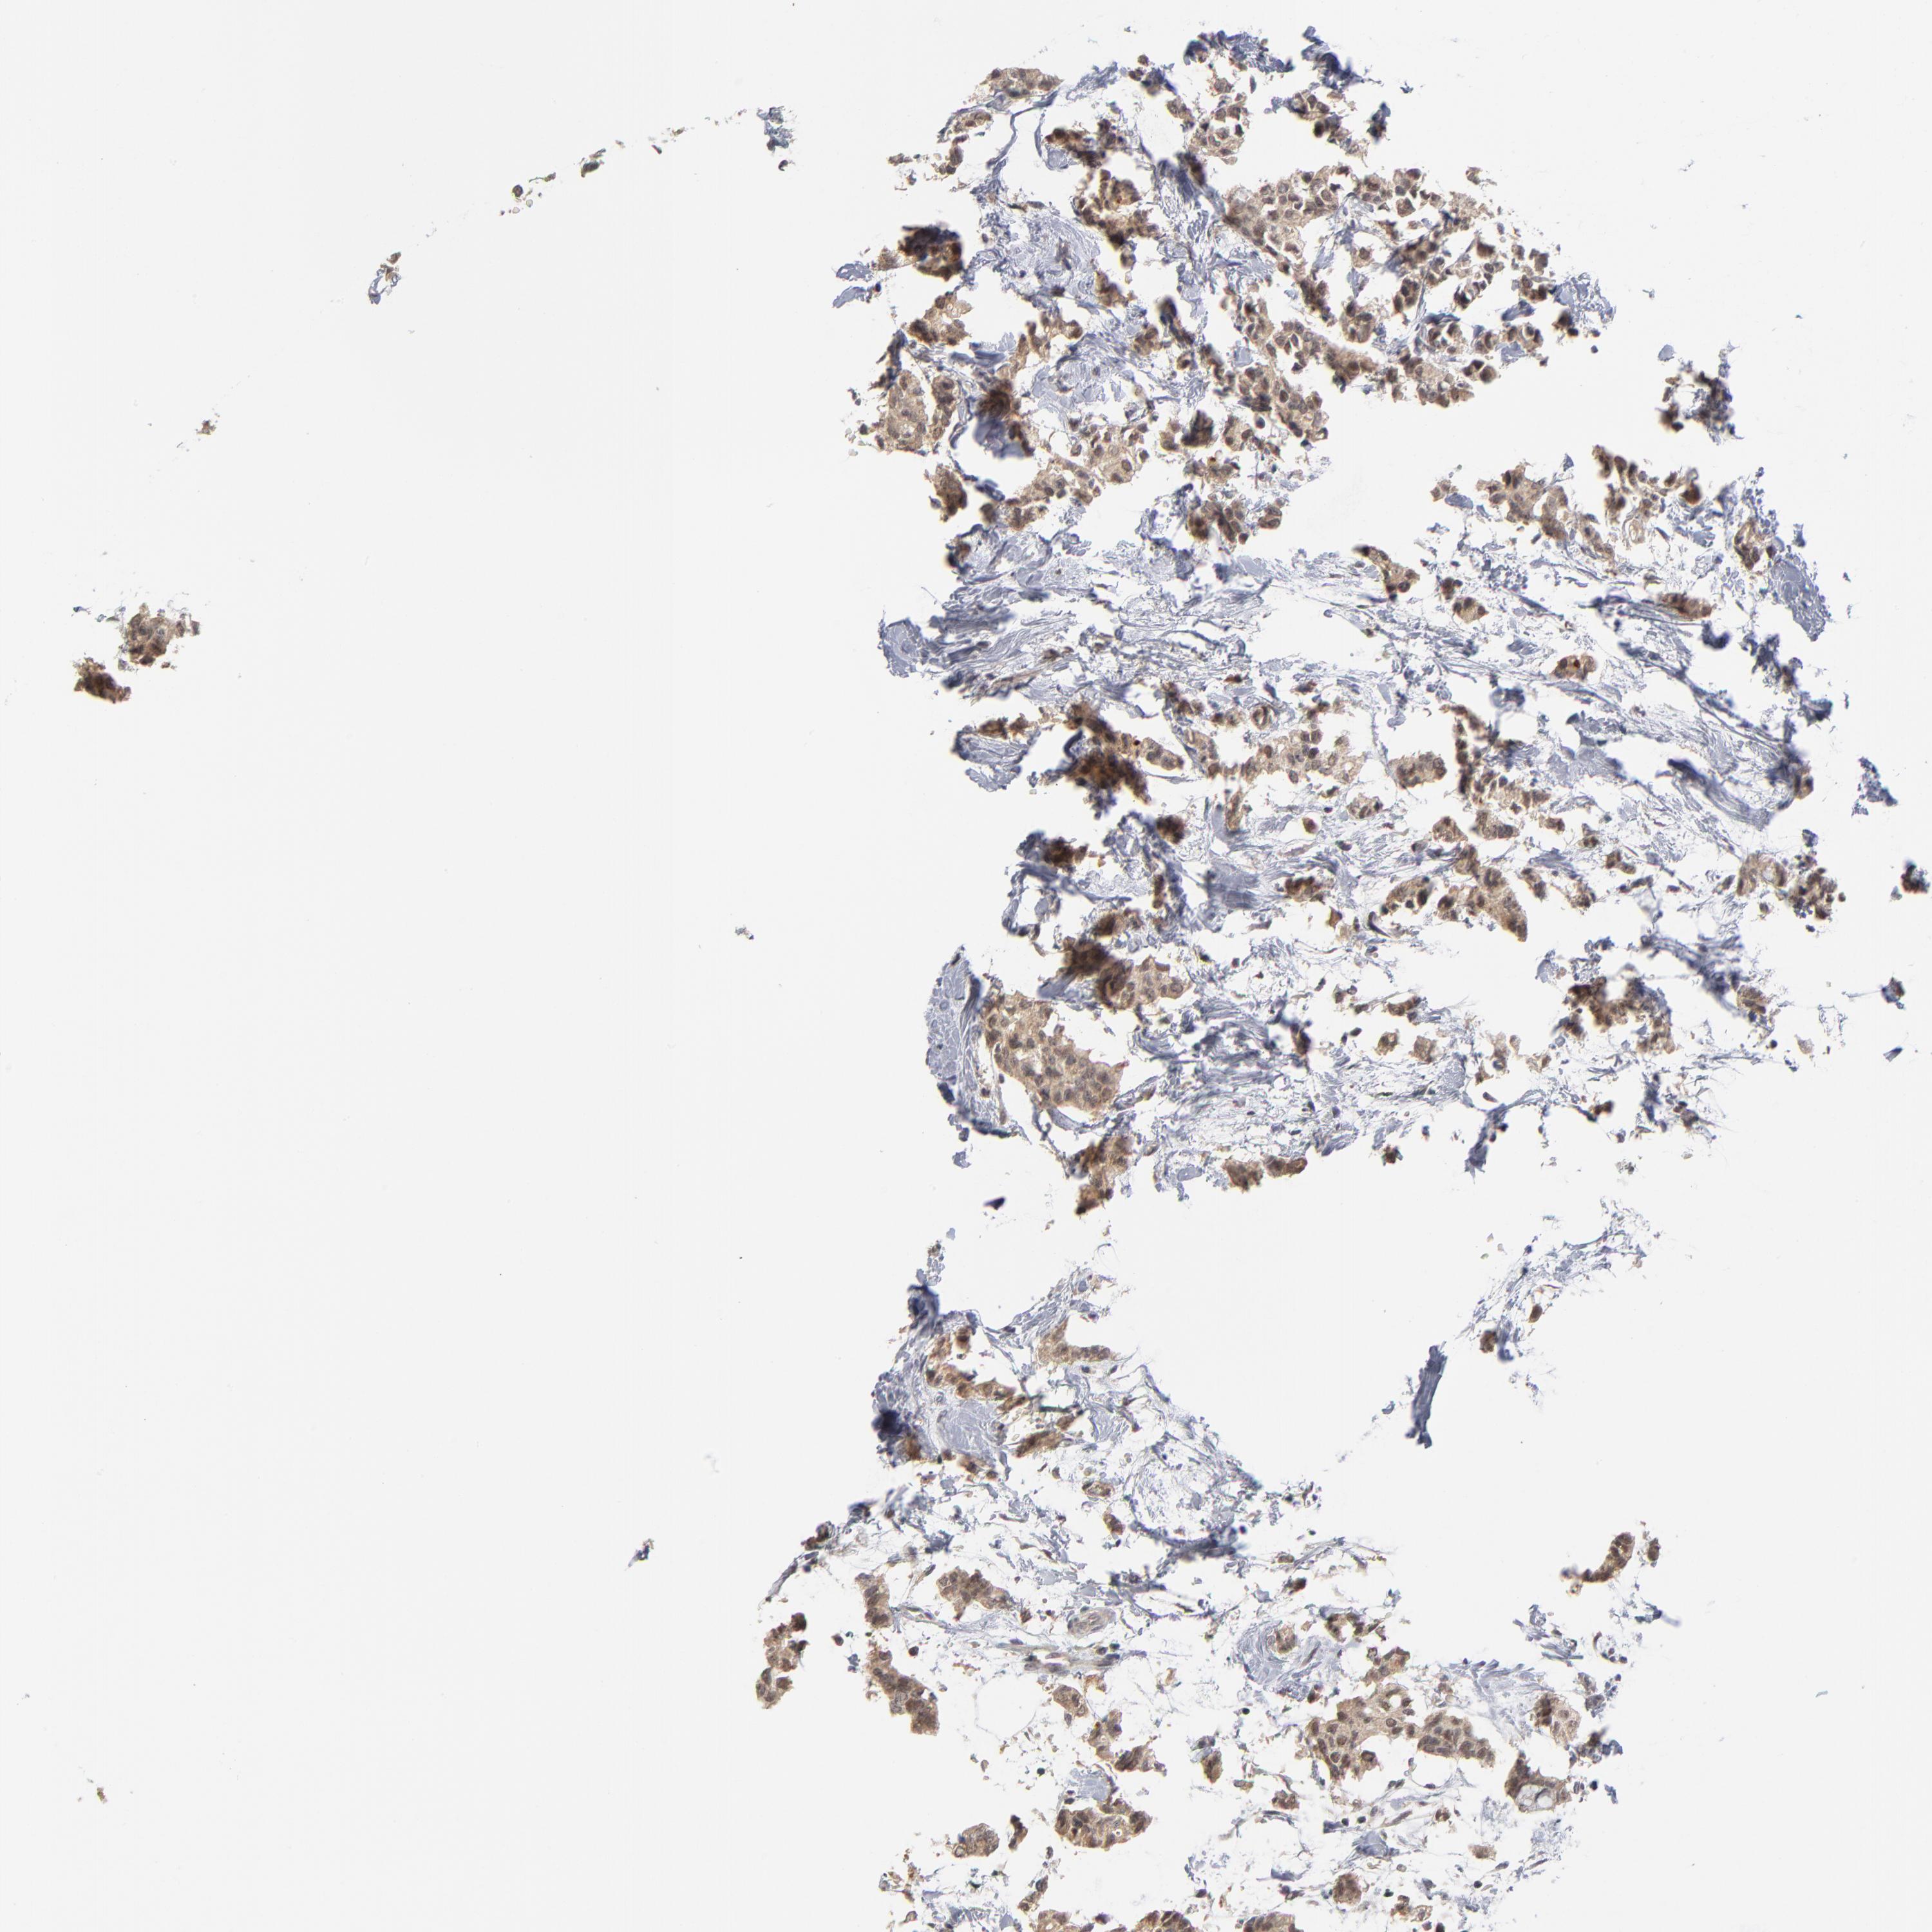

BRCA TCGA BRCA VALIDATION PROTEIN EXPRESSION

ANTIBODIES

AND

VALIDATION